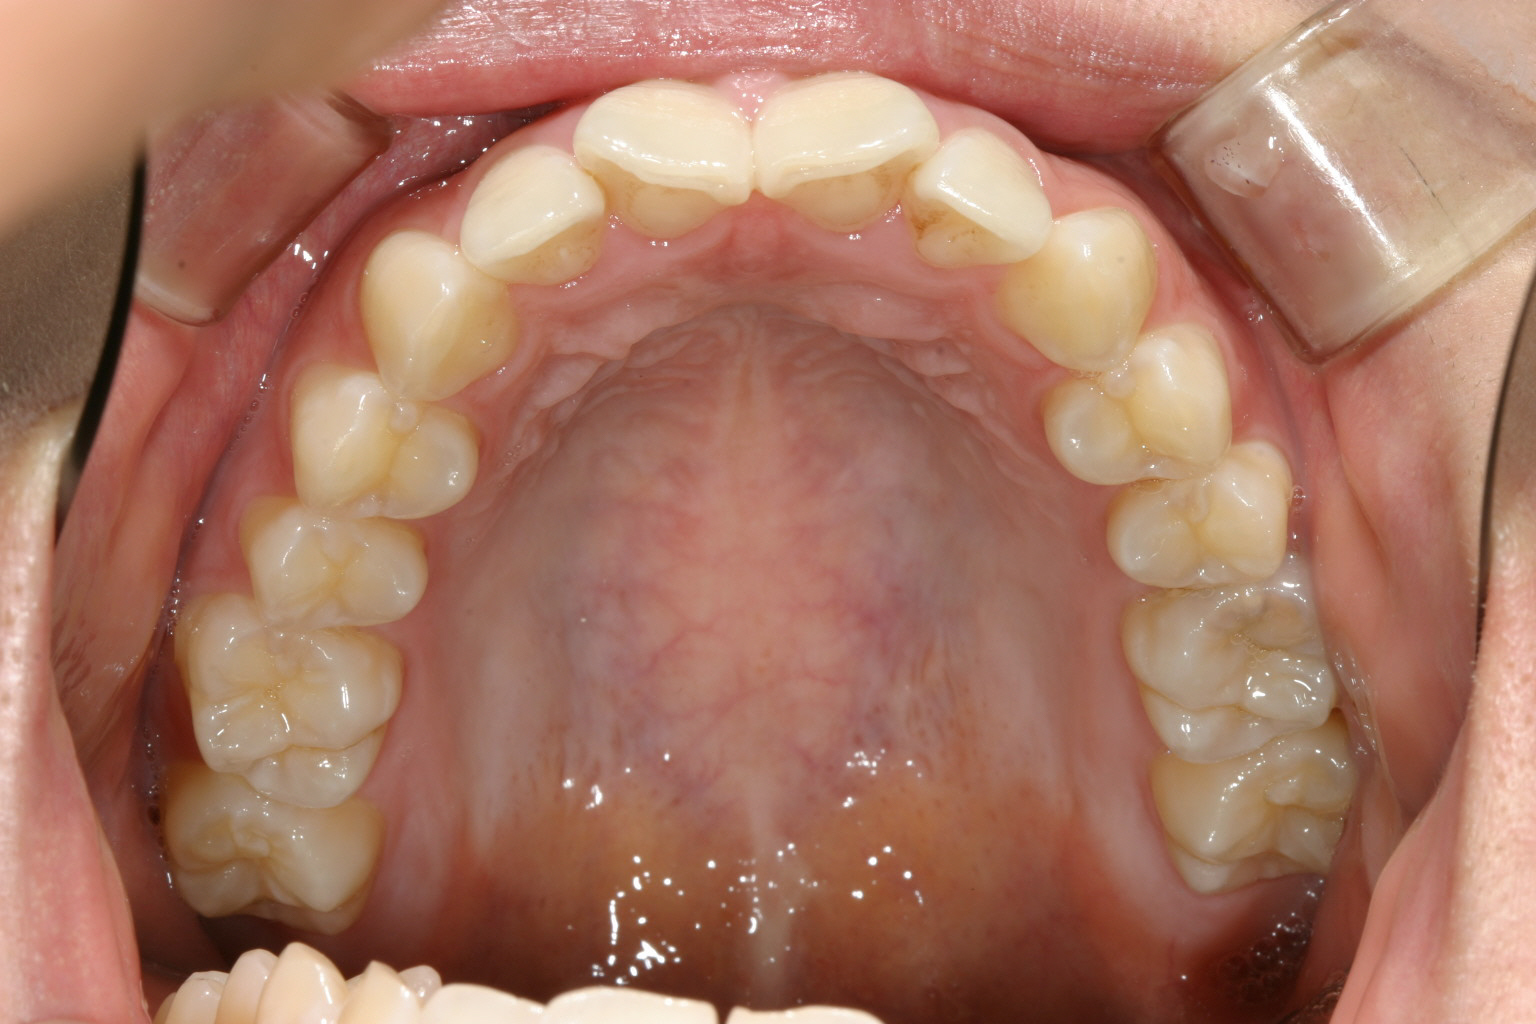

こちらも綺麗なアーチになりました。